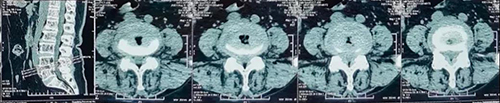

腰椎病例是66岁女性患者,主诉“腰痛10余年,加重5年,双下肢疼痛4年”。查体显示腰椎屈曲活动受限,腰部棘突,椎旁肌无明显压痛,叩击痛。腰椎MRI显示L4/5椎间盘突出并黄韧带肥厚并椎管狭窄。诊断为腰椎管狭窄症,腰椎间盘突出症,高血压病,Ⅱ型糖尿病。

该患者为腰椎间盘突出所致椎管狭窄,L4/5椎间隙退变严重,需要进行腰椎减压椎间融合手术,需要近期的可靠稳定及远期的牢固融合。这种腰椎融合手术一般应用不同规格的PEEK材料椎间融合器,因其椎间融合器上下仅两面植骨及通体无微孔结构,骨接触面积小,术中即刻稳定性及术后远期骨性融合效果往往不佳。丰荣杰主任医师决定为患者采用3D打印钛合金椎间融合器,进行腰椎后路减压植骨融合内固定术。该手术可在融合器前后左右360°以及上下两个面与椎体终板及周围骨质形成全方位无间隙的融合,有效增加骨接触面积,利于自体骨的长入。同时,3D打印钛合金融合器更加接近人体正常骨质的弹性模量,有效避免应力遮挡及骨吸收,与人体骨质有效融合,获得良好的即刻稳定性和远期的牢固骨性融合效果,避免骨性不融合、断钉、断棒等并发症的发生,进一步增加手术效果及手术安全性。

术前CT